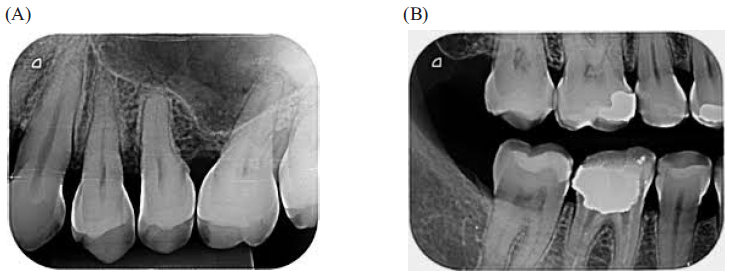

Identifique, nas imagens, os tipos de radiografias intraorais:

Fonte: Google imagens

Assinale a alternativa CORRETA: